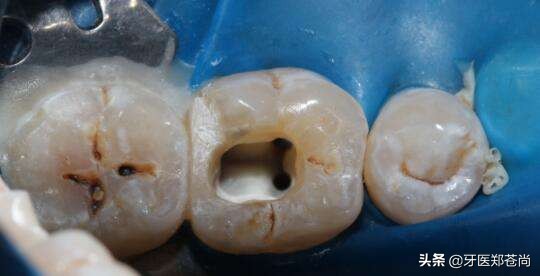

根管治疗后的牙齿

根管填充,治疗中将根管内病变组织清理出来后,会对根管进行填充。

做牙冠,也有的是做嵌体,其目的是防止患牙劈裂,同时防止外界细菌进入到牙齿内部。